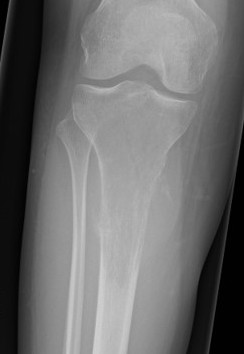

Osteosarcomas of the proximal tibia